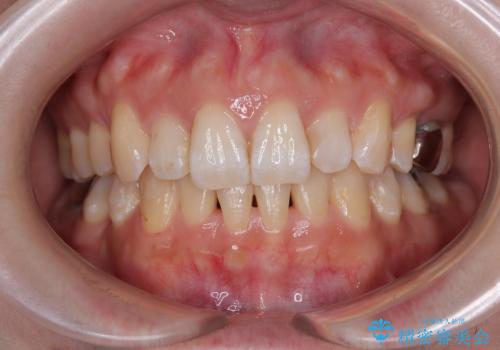

- 前歯のデコボコを気にして来院された患者様です。

非抜歯矯正にて治療を行うと、仕上がりで口元が突出する可能性があったため、小臼歯抜歯での矯正治療を行うこととしました。

上顎は左右の第一小臼歯2本を、下顎は左右の第二小臼歯2本を抜歯して、口元が突出しないようにしながら、奥歯の咬み合わせを改善していく治療計画としました。

目立たない装置が希望であったため、上顎が裏側装置である、ハーフリンガル装置を選択されました。

第二小臼歯抜歯としたため、治療期間は長くなりましたが、満足のいく仕上がりとなりました。